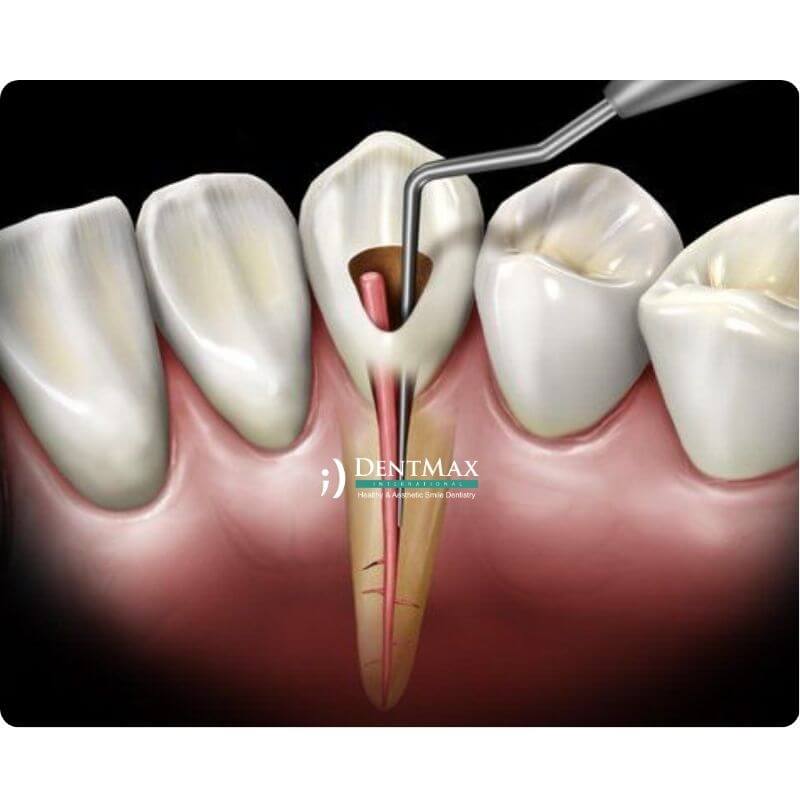

• Kök kanal tedavisi sonucunda rengi koyulaşan dişler.